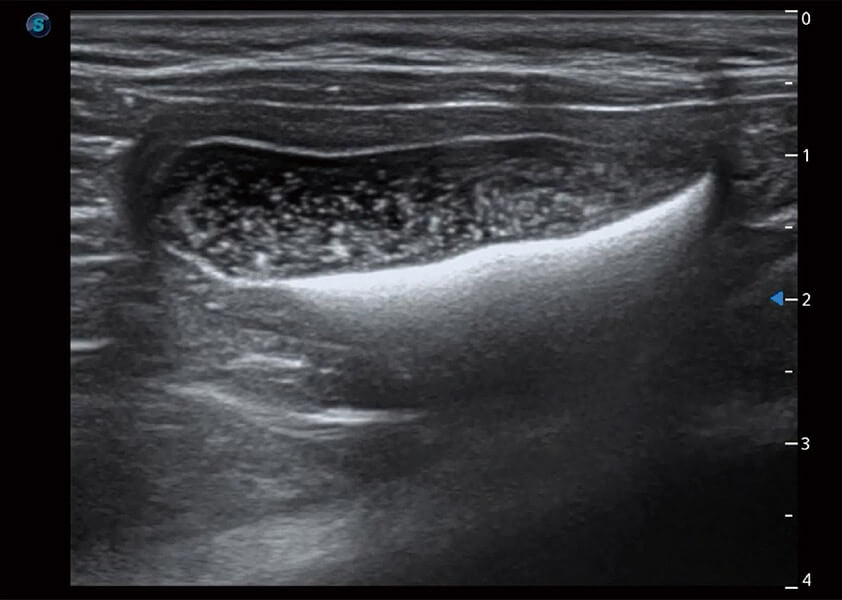

(犬)胆囊泥沙

(猫)膀胱结晶